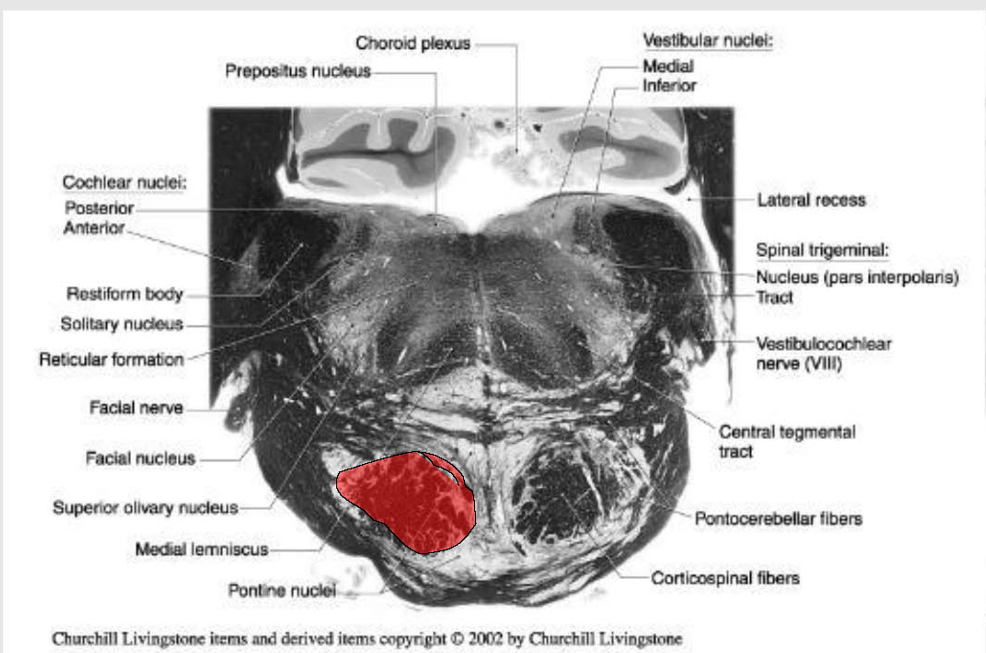

location of major tracts in the Caudal Pons:

CST/corticonuclear (bulbar) run through the substance of the basilar pons

Medial Lemniscus:

still in the midline

begins to turn → somatotopy shifts → leg areas = more lateral

anterolateral system

still in lateral position w/in pontine tegmentum,

@ anterolateral edge w/ formation of middle cerebellar peduncle.

Rubrospinal Tract:

Dorsal to ALS

Reticulospinals and vestibulospinals

still being formed in this area, so they are not clear.

spinal nucleus and tract of CN V

still present as pars oralis

just dorsal to the exit of the facial nerve.

MLF and tectospinal (tectobulbospinal ) tracts

dorsal position near the midline.

will now carry motor information for eye movements.

Other Ascending/Descending → displaced into the pontine tegmentum